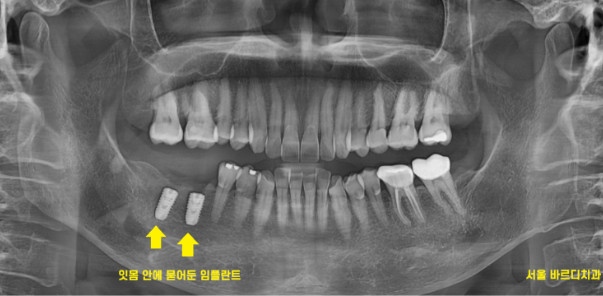

뼈 사진을 보시게 되면

임플란트 잘 심겨져 있답니다.

정확한 것은 x ray를 찍어봐야 상태 파악이 가능하거든요~